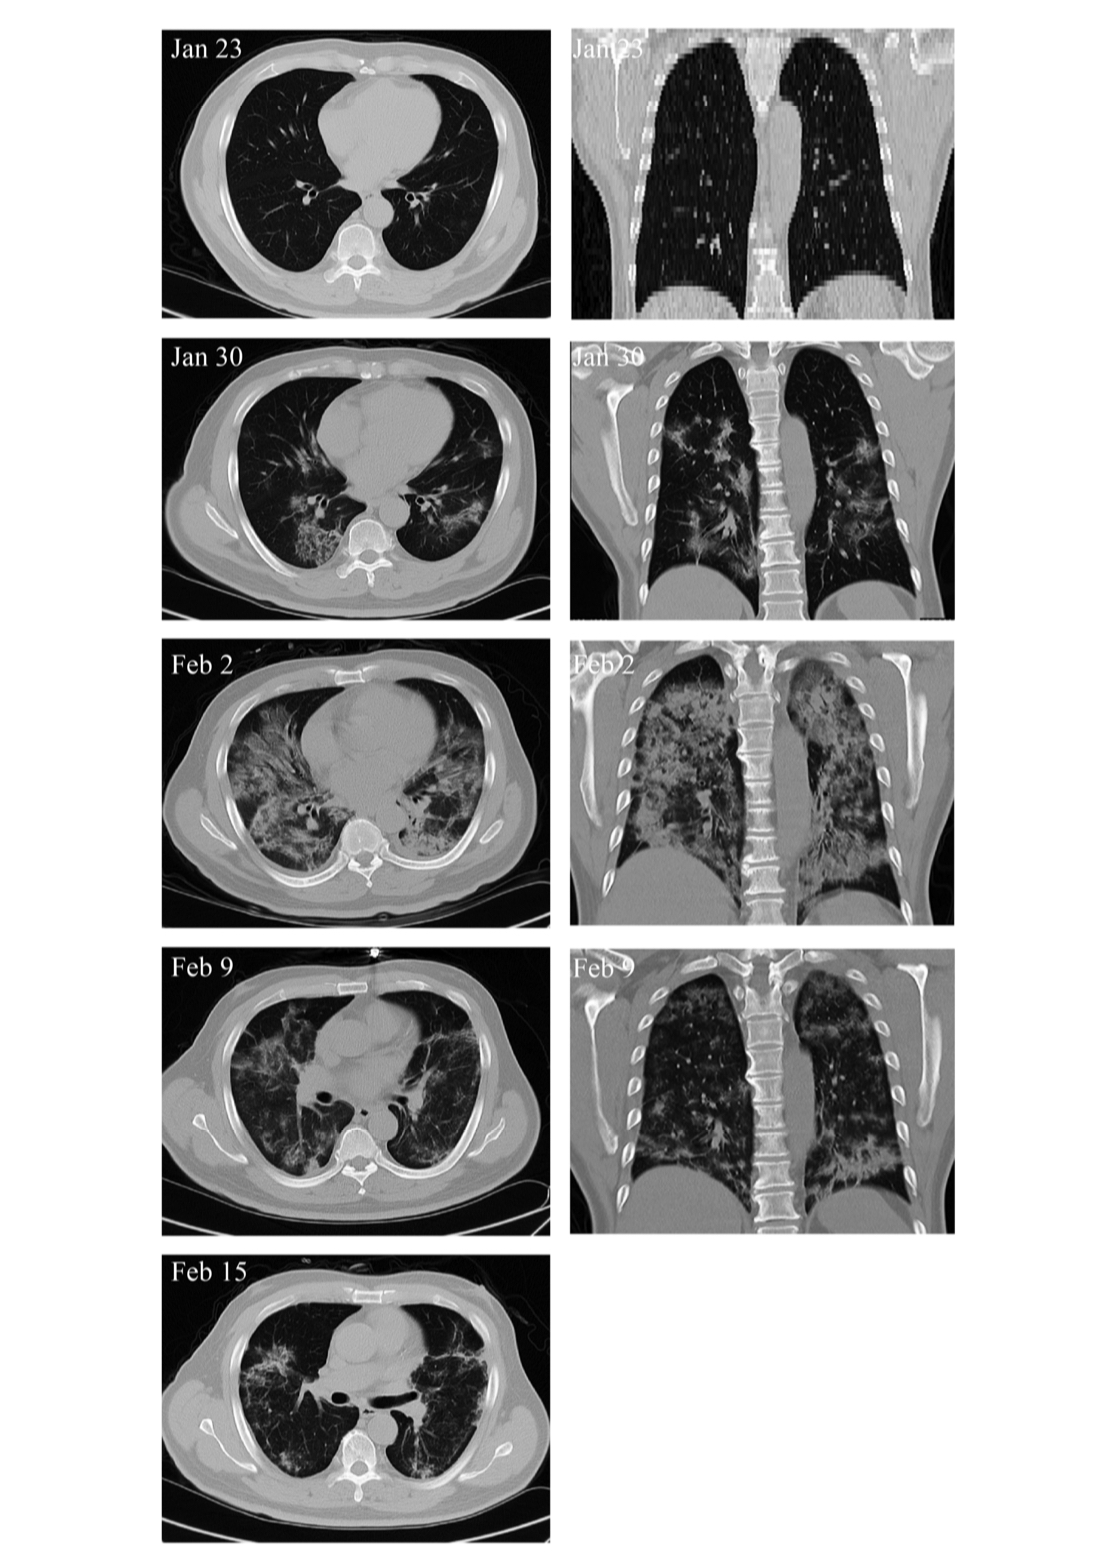

另外,MSC移植能显著加快治疗进程。移植后4天,新冠肺炎危重症患者呼吸频率降至正常范围、发烧和呼吸急促等症状消失。移植后9天,胸部CT成像显示毛玻璃样混浊和肺炎浸润已大大减少。

危重患者肺部影像学显示症状改善